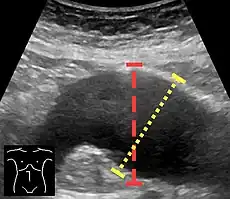

Aortic measurement on abdominal ultrasonography in the axial plane between the outer margins of the aortic wall.[33] -

Ultrasonography in the sagittal plane, showing axial plane measure (dashed red line), as well as maximal diameter (dotted yellow line) which is preferred. -